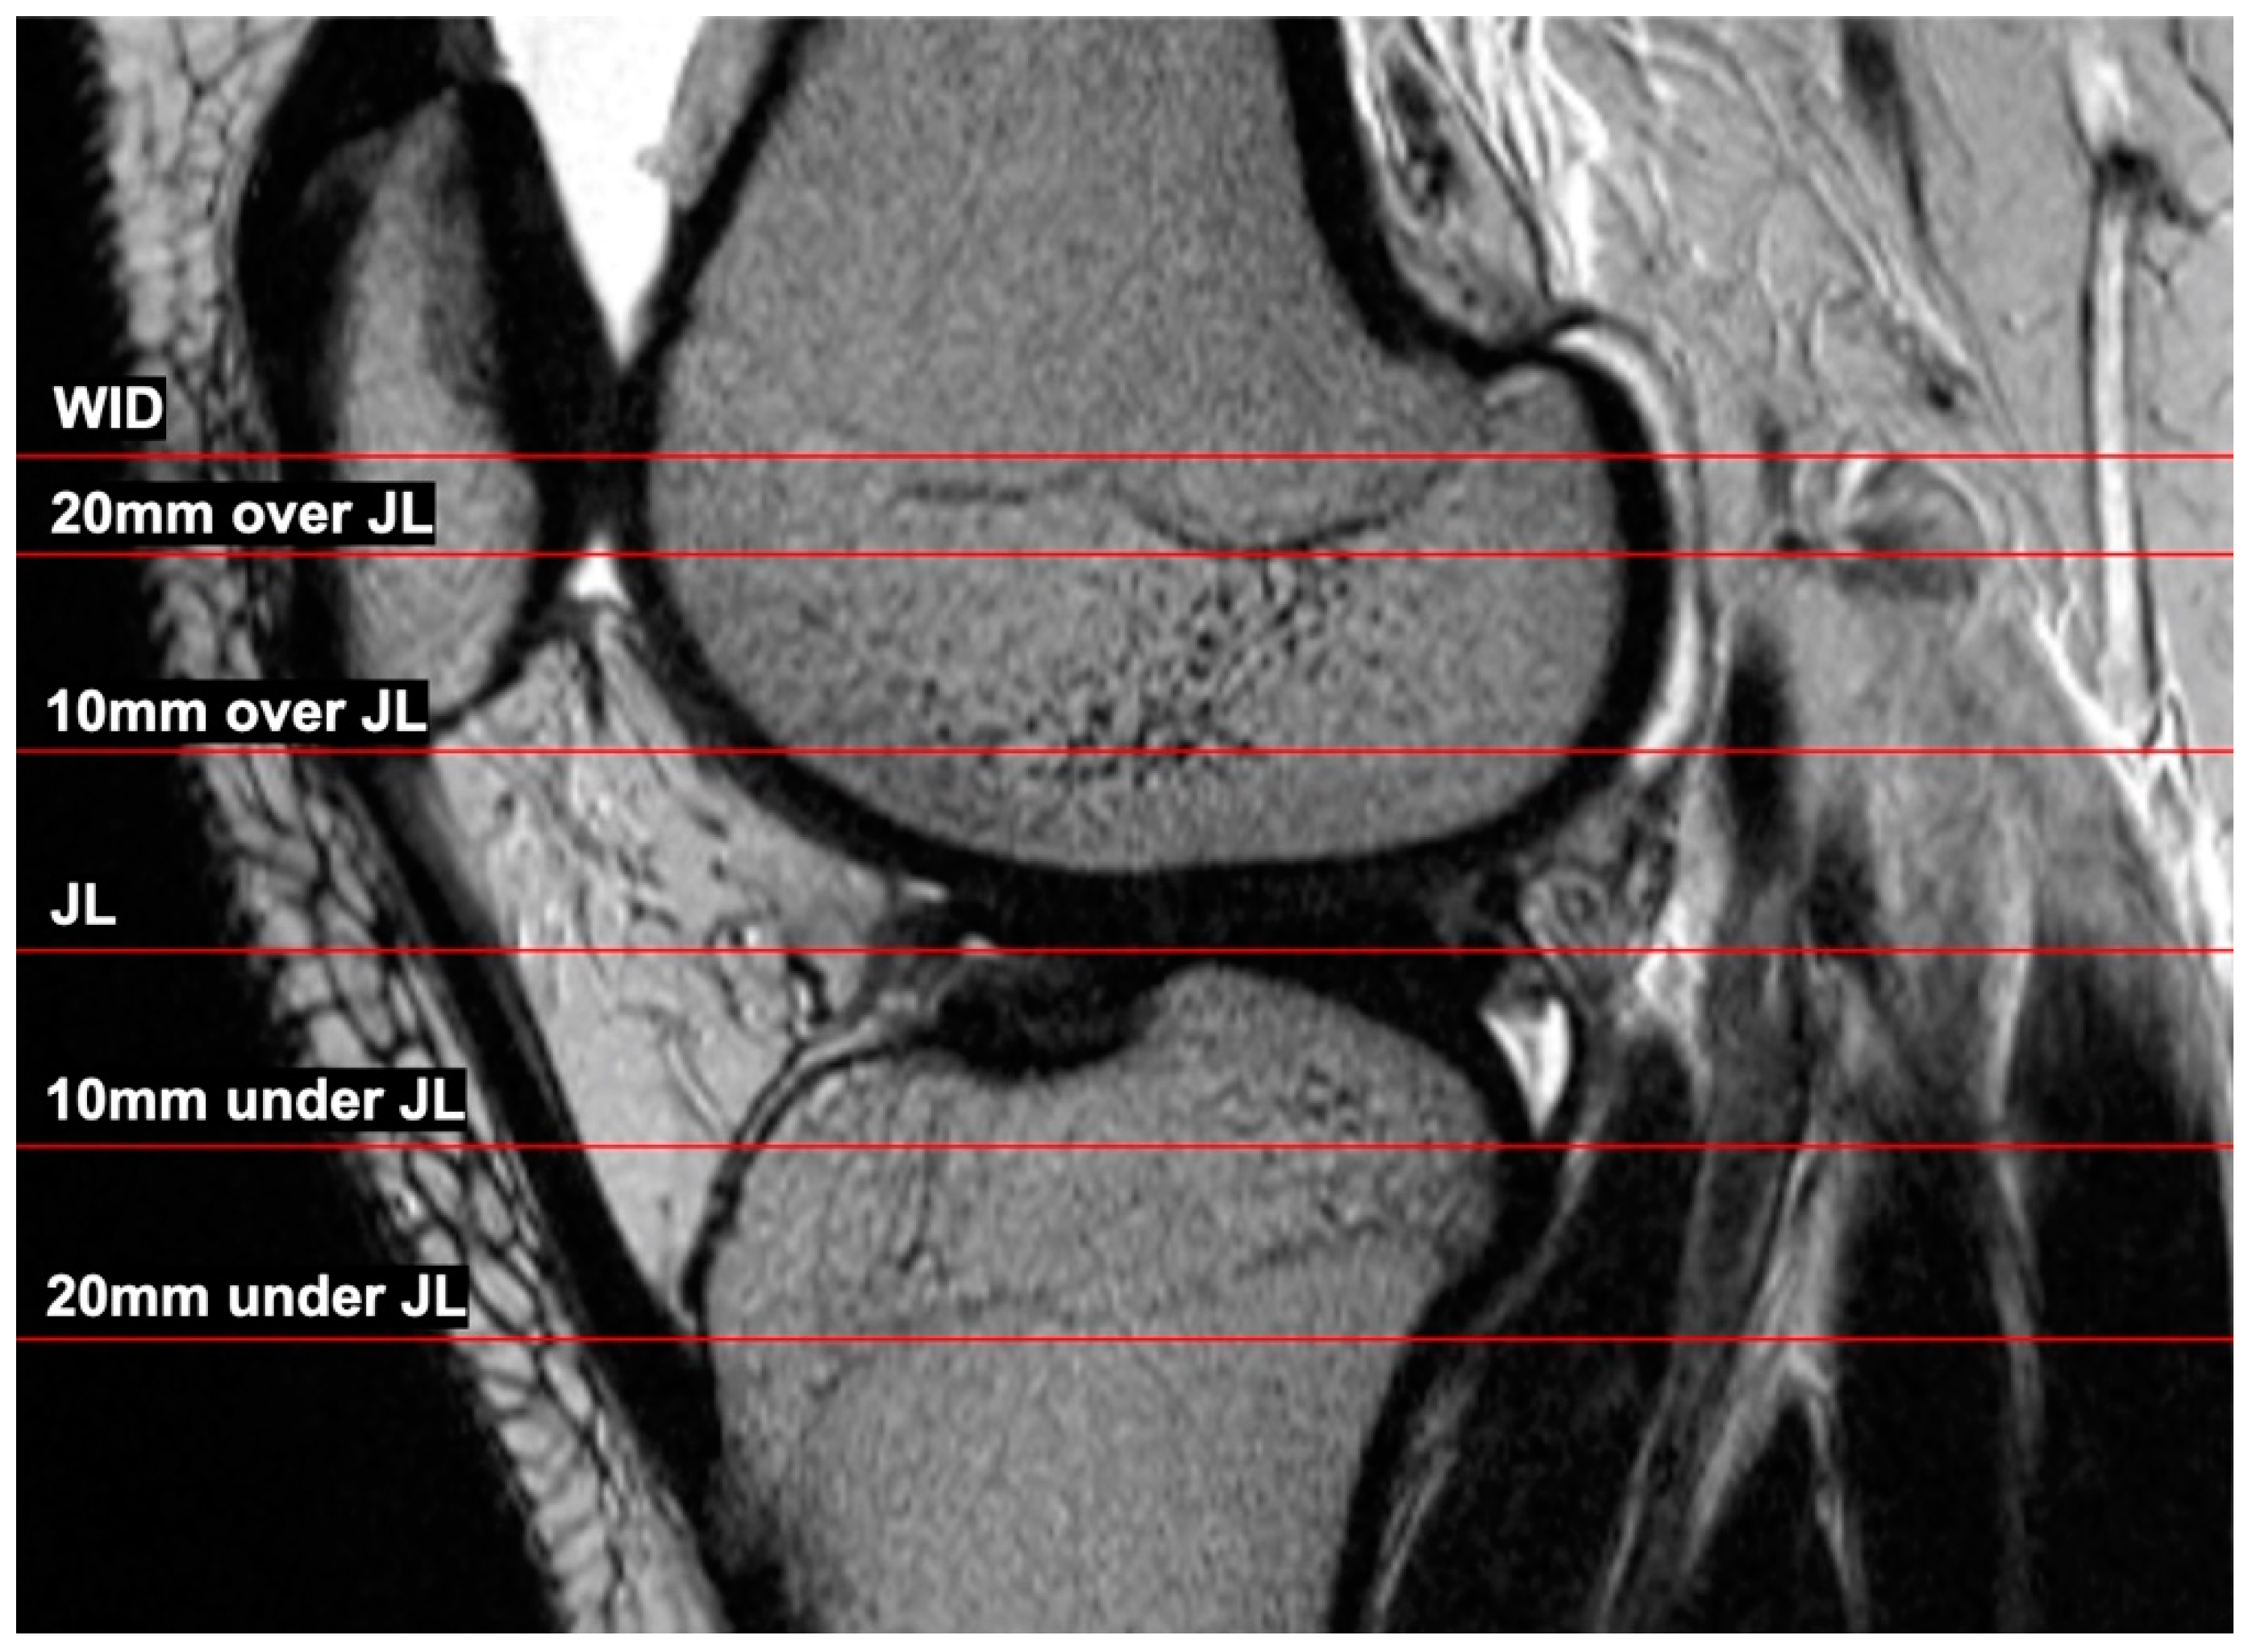

2.2. MRI Measurements

- Level of the widest intercondylar dimension (WID);

- 20 mm over joint line (20 mm);

- 10 mm over joint line (10 mm);

- Joint line level (JL);

- 10 under joint line (−10 mm);

- 20 mm under joint line (−20 mm).